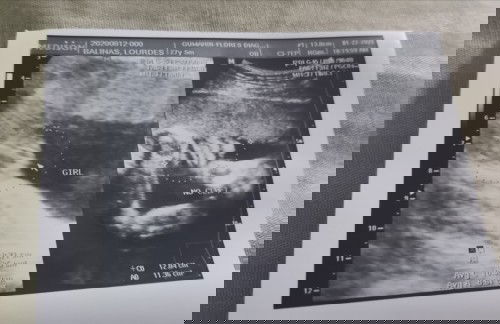

Hello po mga mommies, as lang po ako if meron din po bang same experience sakin na nag spotting (pics) at 5 months? first time po kasi sakin at niresetahan ako ng Heragest up to 28 weeks.. Share naman po ng experience takot pa din kasi ako. ##firstbaby #1stimemom #advicepls #theasianparentph